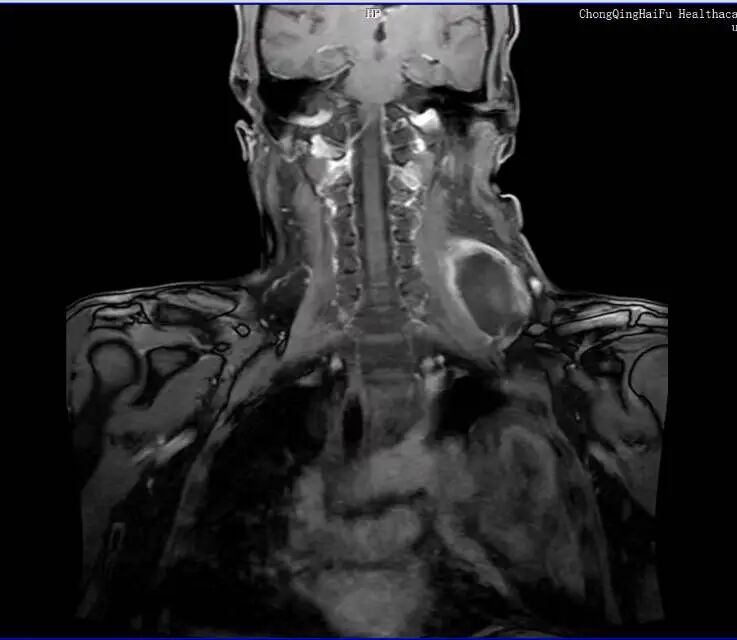

2025 年肿瘤再次复发,多处出现转移灶,2026 年颈部又长出鸡蛋大小肿块,辗转多家医院,因已是脂肪肉瘤Ⅳ期、多发转移,反复手术和化疗让身体难以耐受。

复查 MRI 显示肿瘤消融范围理想,病灶无灌注区清晰可见,远超预期。手术过程十分顺利,术后患者生命体征平稳,术后第一天,患者疼痛就明显缓解,精神、饮食都恢复良好。